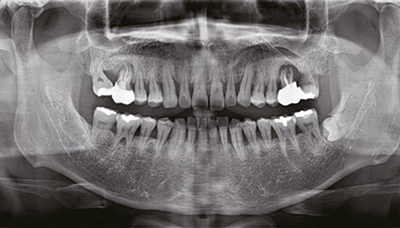

Пародонтология

Максимально чёткое и чистое изображение без искажений для наилучшей диагностики даже при использовании максимальной зоны сканирования.